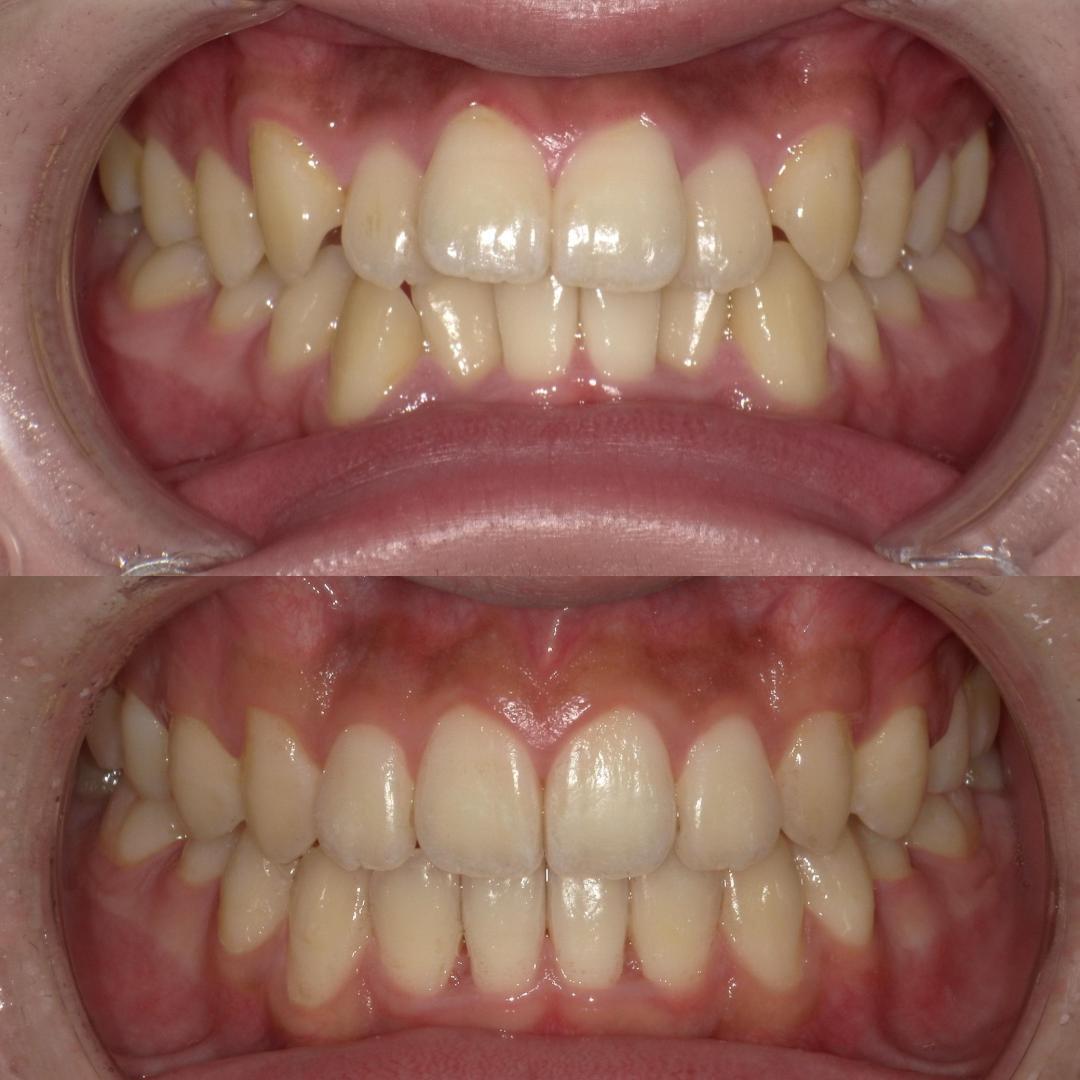

そういった様々な要因を取り除くことで、従来、小臼歯(4番、5番)を抜歯しなければ治療できない症例でも、非抜歯で治療可能となってきているのです。

機能的に小臼歯は非常に大切な歯であることから、最大限小臼歯を抜歯せずに治療できる治療方針を考えます。

また、下顎の位置関係、歯の傾きなどの原因を新素材ゴムメタルワイヤーで治療を行うことでほとんどの症例で小臼歯を抜歯しなくても治療可能になってきています。